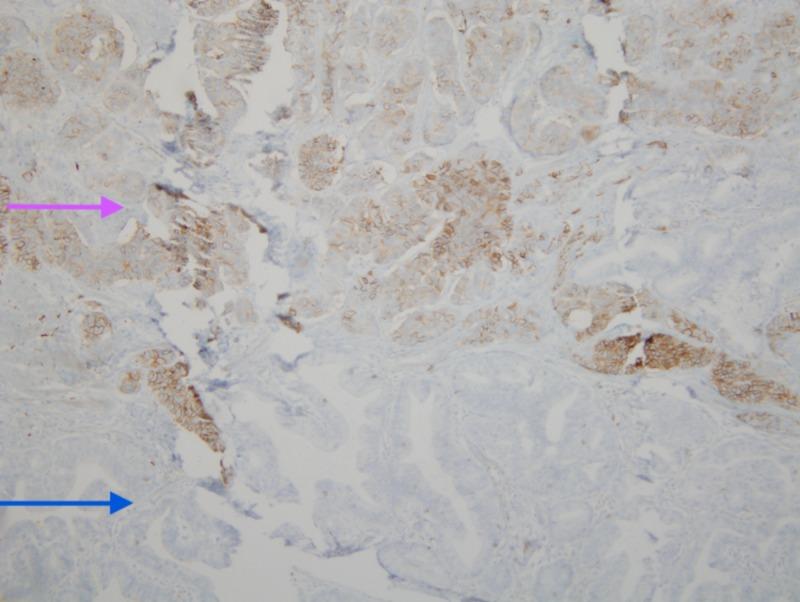

Neuroendocrine tumors (NETs) of gastrointestinal tract are rare entities. Their presence as synchronous lesions with adenocarcinoma has rarely been described in the literature. Cases of synchronous lesions of adenocarcinoma with neuroendocrine component have been described in the colon in the past. However, synchronous presence in the ampulla of Vater is quite uncommon. In the duodenum, NETs constitute 5.7 to 7.9% of the neuroendocrine neoplasms of the gastroenteropancreatic tract. We present a case of 65-year-old male who presented with abdominal symptoms and weight loss, was found to have adenocarcinoma of the ampulla of Vater on biopsy via endoscopic retrograde cholangiopancreatography (ERCP), for which he underwent Whipple's surgery and was found to have neuroendocrine component along with adenocarcinoma postoperatively on histology.

胃肠道神经内分泌肿瘤(NETs)是罕见的疾病。它们作为与腺癌同步出现的病变在文献中很少被描述。过去曾有过结肠中腺癌与神经内分泌成分同步病变的病例报道。然而,在 Vater 壶腹出现同步病变相当罕见。在十二指肠,NETs 占胃肠胰道神经内分泌肿瘤的 5.7%至 7.9%。我们报告一例 65 岁男性,因出现腹部症状和体重减轻就诊,经内镜逆行胰胆管造影术(ERCP)活检发现患有 Vater 壶腹腺癌,为此他接受了 Whipple 手术,术后组织学检查发现除腺癌外还存在神经内分泌成分。